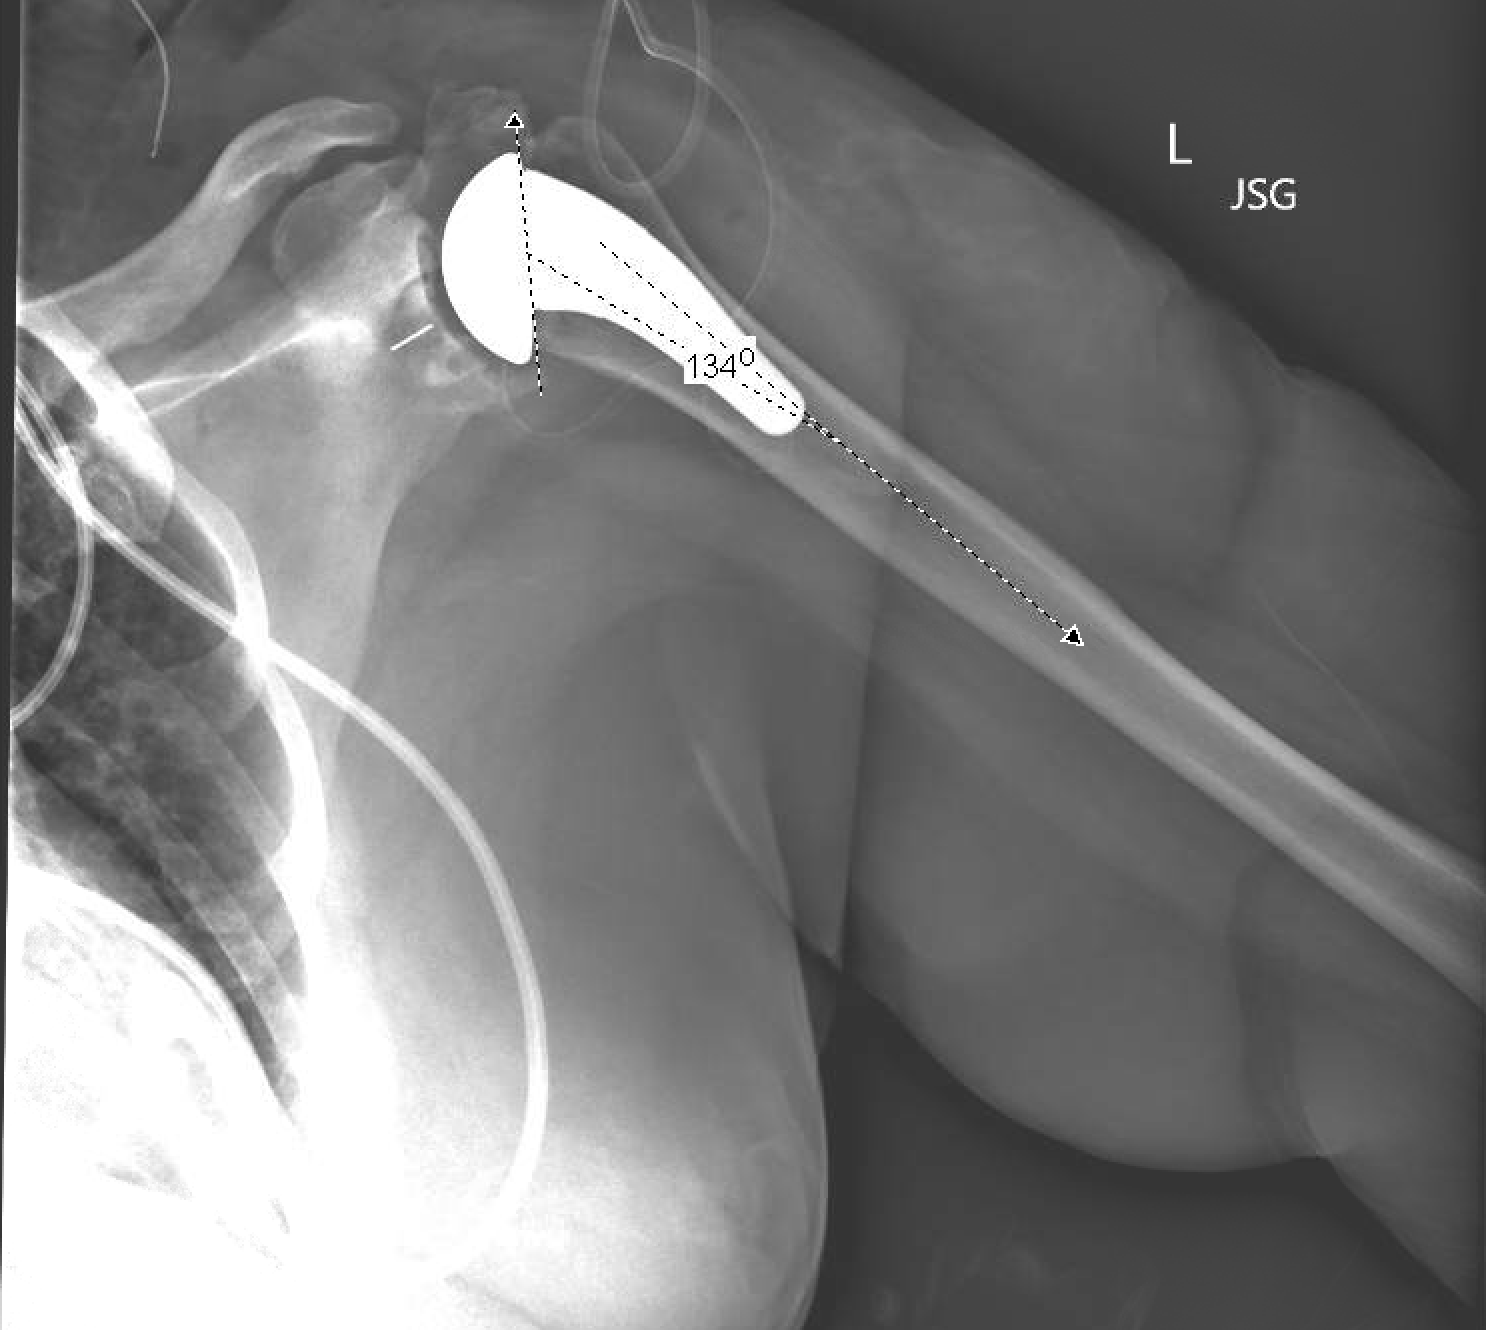

Clinical and radiological of a stemless reverse shoulder What Is A Stemless Shoulder Replacement This technology has been around for many years. Stemless shoulder arthroplasty is a minimally invasive procedure that repairs or replaces an injured shoulder. Anatomic total shoulder arthroplasty is the replacement of the humeral head and glenoid surfaces with the. 4.5/5 (36) What is a stemless shoulder replacement? Shoulder replacement surgery is an operation to replace your damaged shoulder joint. What Is A Stemless Shoulder Replacement.

Clinical and radiological of a stemless reverse shoulder What Is A Stemless Shoulder Replacement This technology has been around for many years. 4.5/5 (36) Stemless shoulder arthroplasty is a minimally invasive procedure that repairs or replaces an injured shoulder. What is a stemless shoulder replacement? Shoulder replacement surgery is an operation to replace your damaged shoulder joint with an artificial joint. Replacement humeral components need to be secured to the bone in the. What Is A Stemless Shoulder Replacement.